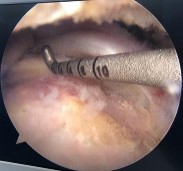

Hình phụ lục 2C: Hình ảnh xác định vị trí đặt 02 neo. (Nguồn: BN nghiên cứu)

Đây là ca lâm sàng điển hình rách hình chữ U theo phân loại của Burkhart, nếu chỉ dựa trên phim CHT trước mổ thì rất khó xác định chính xác hình thái rách và dựa trên phim CHT trước mổ thì tiên lượng khâu được gân rất khó khăn, tuy nhiên sau khi nhận định hình dạng của gân rách chúng tôi tiến hành khâu khép rìa làm thu nhỏ gân rách tạo vi tổn thương tại diện bám, và khâu phục hồi vị trí bám của gân vào củ lớn xương cánh tay bằng 02 neo đôi. Trường hợp rách rất rộng này nếu không tiến hành khâu khép rìa gân rách mà tiến hành khâu kéo trực tiếp đầu gân rách về vùng diện bám sẽ khiến gân căng khó kéo và dễ tạo tai chó hai bên mép của vết rách. Với những trường hợp này khó xác định mốc để đặt neo nếu không dựa vào các mốc và các chỉ số giải phẫu về bờ ngoài gân.